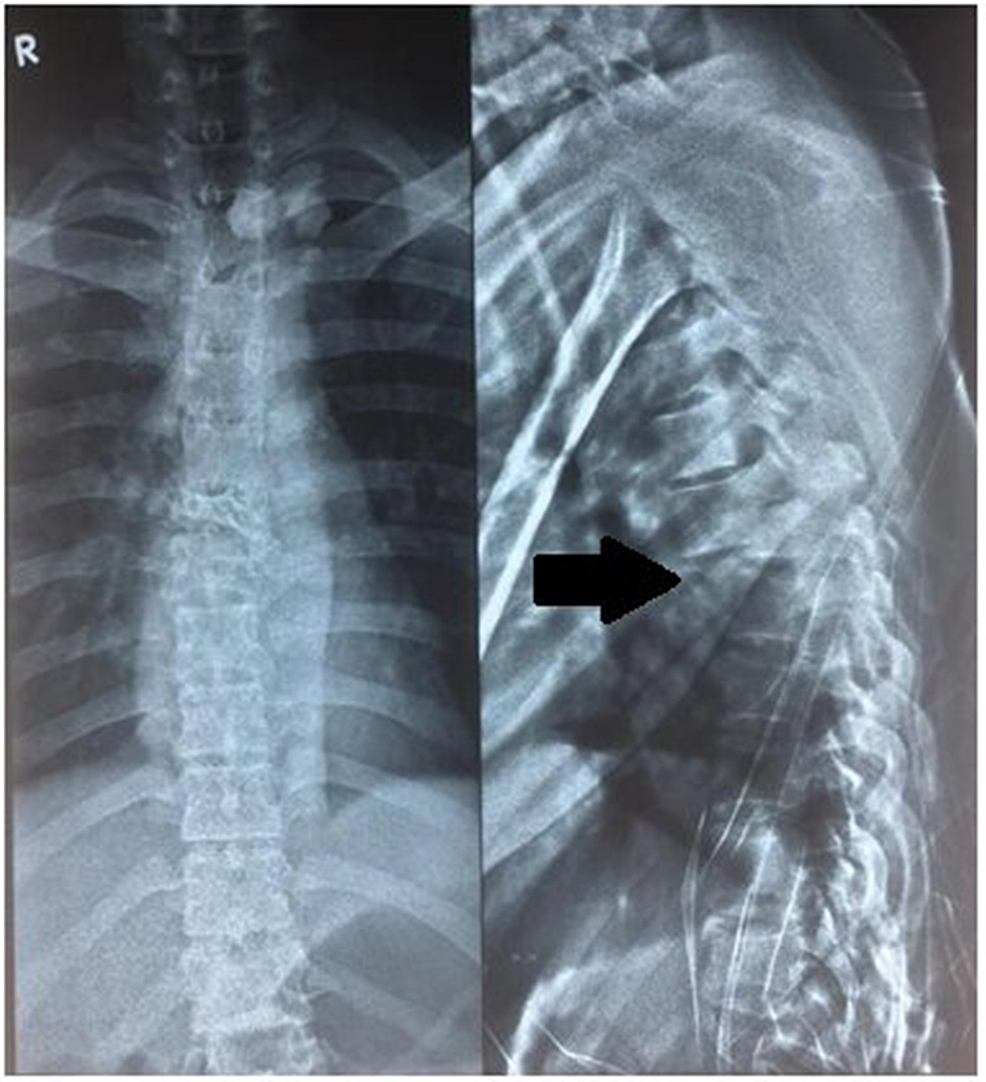

Fracture and bilateral dislocation T6 on T7. Download HighResolution Crush Fracture T6 A crush fracture is characterized by a fracture throughout the entire vertebra, not just the front. They account for only 13% of vcfs. Crush fracture — if the entire bone breaks, rather than just the front of the vertebra, it may be called a crush fracture. The least common vcfs are crush compression fractures. In this type of compression. Burst. Crush Fracture T6.

(a) Anteroposterior and (b) lateral radiographs of the thoracic spine Crush Fracture T6 They account for only 13% of vcfs. Crush fracture — if the entire bone breaks, rather than just the front of the vertebra, it may be called a crush fracture. In this type of compression. A crush fracture is characterized by a fracture throughout the entire vertebra, not just the front. The least common vcfs are crush compression fractures. Burst. Crush Fracture T6.